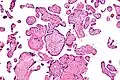

Intermed. mag.

High mag.

VUE can be of 2 types, low grade chronic villitis or high grade chronic villitis. Low grade chronic villitis involves less than 10 villi containing lymphocytes. Low grade chronic villitis can be either focal or multifocal. Focal has involved villi on only one glass slide, while multifocal has involved villi on at least two slides. High grade chronic villitis has more than 10 inflamed villi per focus. High grade chronic villitis is differentiated into diffuse and patchy. The term patchy is used if less than 30% of distal villi are involved. The term diffuse is used if more than 30% of distal villi are involved.

VUE does not have specific clinical signs and symptoms suggesting diagnosis; but an analysis of the inflammatory filtrate can aid in diagnosis.[1] The composition of inflammatory infiltrate in VUE on a cellular level is primarily macrophages and lymphocytes. The relative proportions of cells vary case by case. The lymphocytes present in VUE are predominantly CD8+ T-cells then CD4. There is usually a ratio of 0.1 to 0.5 for CD4/CD8.[17][18] The macrophages present are mainly Mac387-, followed by CD68 and HAM56+. Class 2 major histocompatibility complex (MHC) antigens on macrophages are up-regulated at sites of VUE. Neutrophils should not be present at sites of VUE. VUE is a condition involving inflammation and not infection. High numbers of neutrophils are present in infectious villitis and not VUE.[1][14]

Histomorphologically, VUE is characterized by a lymphocytic infiltrate of the chorionic villi without a demonstrable cause. Plasma cells should be absent; the presence of plasma cells suggests an infective etiology, e.g. CMV infection.